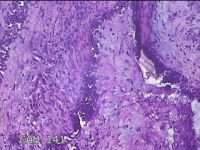

右侧卵巢囊肿

性别

女

年龄

36岁

临床诊断

一般病史

发现双侧附件囊肿1年。

标本名称

大体所见

灰白暗红色囊壁样组织2.5x2x0.3cm一块,表面光滑,部分已切开,囊内容物已流失,囊壁厚0.2cm。

考虑:子宫内膜异位囊肿。